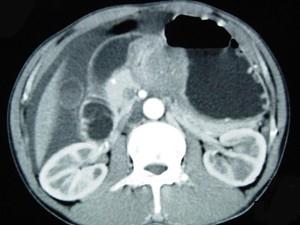

问题 男,65岁,中上腹痛腹胀、消瘦、乏力、纳差,影像检查如图,最可能的诊断是 ( )

选项 A、胃窦癌 B、胃淋巴瘤 C、萎缩性胃炎 D、肥厚性胃炎 E、胃间质瘤

答案 A